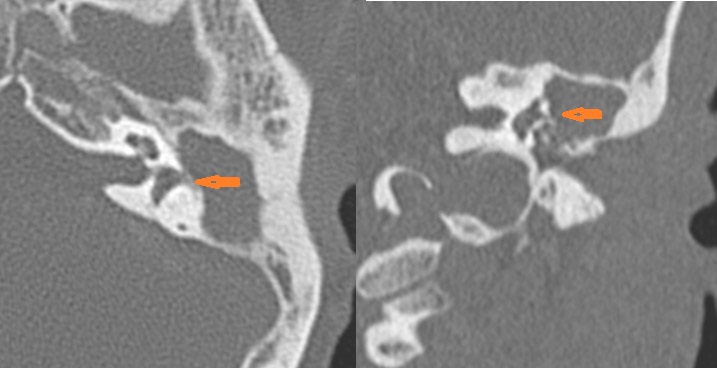

The ossicles; in particular the incus long process, the incudostapedial joint and stapes are eroded or displaced.